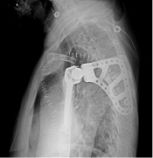

KORDOMA

Grafide sakrumda orta hat yerleşimli, belirsiz sınırlı, litik bir kitle görülür. Düz grafide görüntü almak çok zordur. MRI incelemesi, tümörün tüm uzanımını, öndeki rektum, mesane, damarlar ve özellikle sinir kökleri ile ilişkisini gösterir. BT’de kemikteki destrüksiyon en iyi şekilde görülür. Ayırıcı tanıda dev hücreli tümör, anevrizmal kemik kisti, kondrosarkom dikkate alınmalıdır.

Kordomada kemoterapi ve radyoterapinin etkisi yoktur, buna karşın lokal tekrarlama eğilimi çok yüksektir. Yetersiz cerrahi yapıldığında lokal nüks gelişir. Esas tedavisi cerrahidir. İmkan dahilinde geniş rezeksiyonla çıkartılmalıdır. Teknik olarak tam çıkartılamaz ise radyoterapi (RT) uygulanmalıdır. Geniş rezeksiyon yapıldığında 5 yıl yaşam şansı %73, 10 yıl yaşam beklentisi %58’dir. Hastaların %30’unda metastaz görülür.